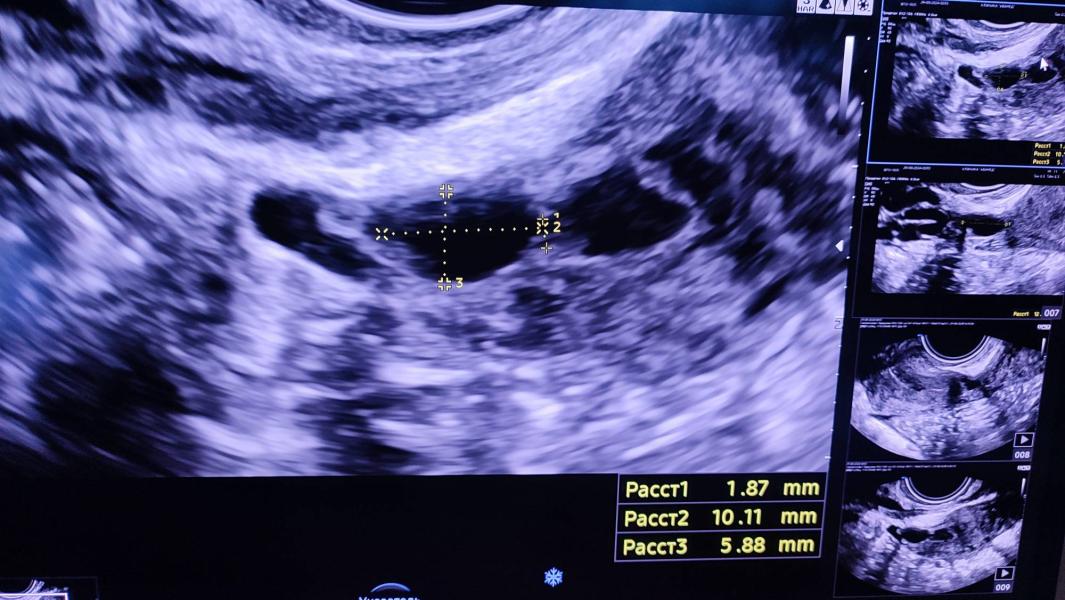

Пациентка после фарм аборта в сроке 8 недель беременности по поводу анэмбрионии ( отсутствие эмбриона в плодном яйце).

В полости матки остатки плодных оболочек, с последующим образованием плацентарного полипа, который питается сосудистой ножкой. В анамнезе одна операция кесарево сечения: в области рубца отмечается дефект передней стенки перешейка матки. В данном случае нужно провести гистероскопию с последующей метропластикой. Беременность с данным дефектом может привести к разрыву матки по ...